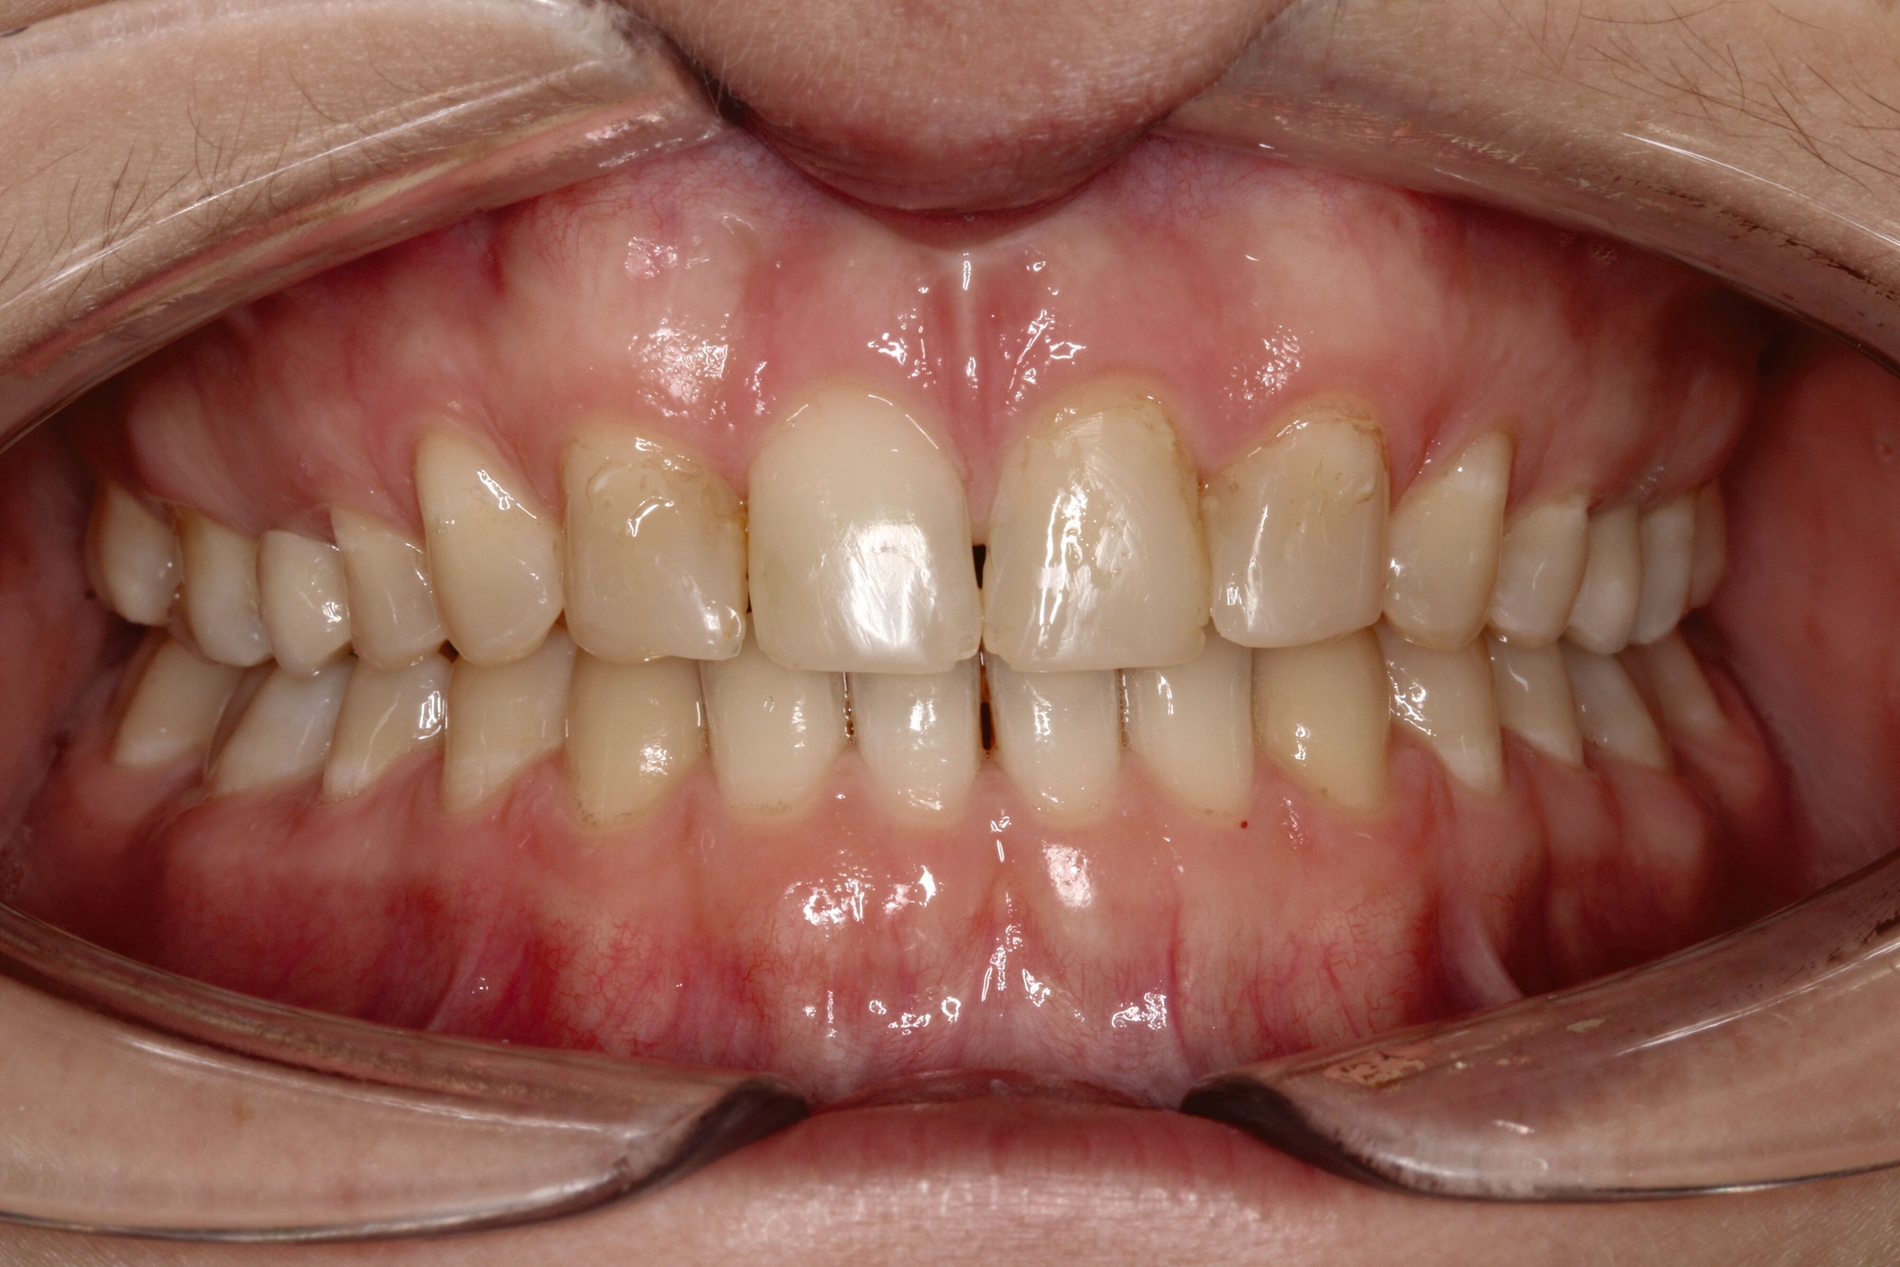

Bei dem gut zwölfjährigen Mädchen sind die seitlichen oberen Schneidezähne (Zähne 12 und 22) nicht angelegt. Zusätzlich zeigten sich verlagerte zweite obere Prämolaren.

Im vorliegenden Fall stand der Zahn 23 bereits im Mesialstand bei hoher Lachlinie und tendenziell konkavem Lippenprofil. Bezüglich Morphologie und Farbe waren die Zähne 13 und 23 nicht ausgeprägt eckzahntypisch. Es bestand kein Platzmangel im Gegenkiefer. Die Patientin war bei der Erstdiagnose 12,5 Jahre alt und im Wechselgebiss der zweiten Phase mit atypischer Durchbruchreihenfolge. Es bestand eine geringfügige Klasse II. Der Overjet war vergrößert bei vertikaler Wachstumstendenz, der Overbite war um circa einen Millimeter vergrößert aufgrund der geringfügigen Steilstellung der Oberkiefer-Front. Es bestand der Verdacht auf Nichtanlage der Weisheitszähne, 15 und 25 waren verlagert.